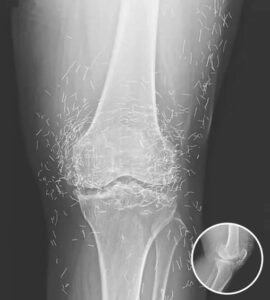

A X-ray of the patient’s knee showing acupuncture needles embedded in the tissue, Photo Credit: Reddit

A routine X-ray revealed an unexpected surprise when doctors examined the knees of a 65-year-old woman suffering from severe joint pain. What they found was nothing short of astonishing — hundreds of tiny gold needles embedded deep in her tissue.

As for the South Korean woman, her case was recently documented in the New England Journal of Medicine. While the needles may have been intended to help, her X-rays tell a cautionary tale about the potential risks of extreme alternative therapies.